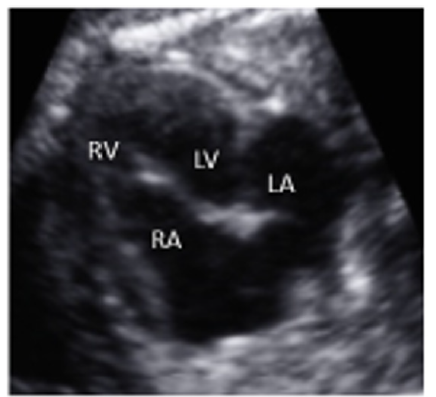

A 35-year-old pregnant woman being in the 29th Gestational Week (GW) was admitted to the Department of Obstetrics and Gynecology of University of Szeged, due to fetal tachycardia with a Fetal Heart Rate (FHR) of 250/min. The mother suffered from hypertension before the pregnancy and underwent calcium channel blocker therapy (Verapamil), which was replaced with methyldopa (Dopegyt) during the pregnancy. Nuchal translucency and biomarkers measured in the first trimester were normal. There was no positive family history for Congenital Heart Defect (CHD). A fetal echocardiography was performed, according to the AIUM guidelines [1]. The FHR was between 240-260/min, the Atrio-Ventricular (AV) conduction was 1:1, a Supraventricular Tachycardia (SVT) was diagnosed (Figure 1). Fetal echocardiography revealed an abnormal four-chamber view, a very large right atrium and a very small right ventricle, the tricuspid valve was abnormal, attached deeply in the right ventricle and the apical displacement of the valve led to the atrialization of the right ventricle and a holosystolic tricuspid regurgitation could be detected by Doppler. The pulmonary artery was very narrow, the diameter of the aorta was twice as big as the diameter of the pulmonary artery, therefore a duct-dependent CHD with decreased pulmonary circulation was suspected. The abnormal anatomy of the fetal heart was characteristic for Ebstein anomaly (Figure 2), which is a complex cyanotic CHD. Pericardial or pleural effusion was not observed, but some ascites was already seen in the abdominal cavity (Figure 3), indicative of incipient fetal heart failure.

Figure 2:Abnormal four-chamber view of the 29 GW old fetus; large right atrium, very small right ventricle, abnormal apical displacement of the tricuspid valve: Ebstein anomaly (RA=right atrium, RV=right ventricle, LA=left atrium, LV=left ventricle).